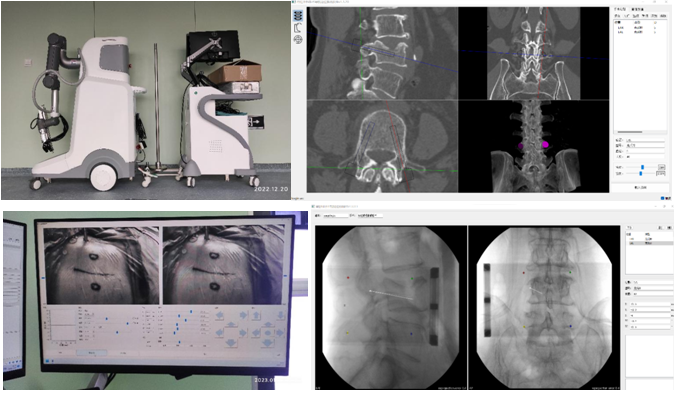

机器人辅助技术是脊柱外科手术向智能化、精准化、微创化发展的又一次飞跃。1月10日,刘时璋主任带领骨科团队精诚合作,在手术室、麻醉科及消毒供应室的鼎力协助下,成功开展21点技巧中心

首例机器人辅助局麻下“经皮球囊扩张椎体成形术(PKP)”治疗腰椎压缩性骨折。此例手术较传统的徒手穿刺更为精准、安全、高效,体现了数字医学与骨科智能化的融合发展。

经MRI及CT检查示:腰4椎体压缩性骨折。经专家讨论后,医疗团队拟采用机器人辅助,局麻下行经皮球囊扩张椎体成形术。经过精密的仪器调试和配准,术前进行了反复的模型演练。刘时璋主任团队将患者的CT数据与机器人系统配准,工程师团队将事先规划好的个体化穿刺路径数据植入机器人系统。将术中的正侧位X线透视数据与CT数据融合后,机械臂按照术前规划路径,一次性穿刺成功,位置精准满意。